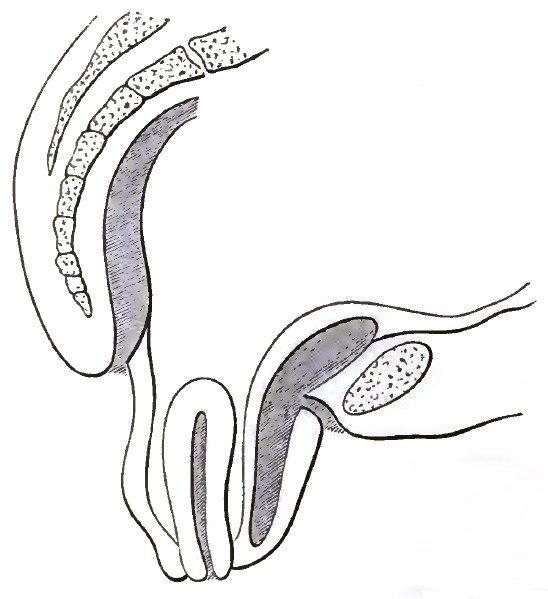

| 15. | EXTREME RETROFLEXION, WITH HYPERTROPHY OF THE CORPUS |

| 16. | COMMENCING REPOSITION OF THE RETROVERTED OR RETROFLEXED UTERUS BY CONJOINED MANIPULATION |

| 17. | COMPLETED REPOSITION OF THE RETROVERTED OR RETROFLEXED UTERUS BY CONJOINED MANIPULATION |

| 18. | SHOWING THE PELVIC ORGANS SUSTAINED BY THE EMMET PESSARY AFTER REPOSITION OF THE PROLAPSED, RETROVERTED, OR RETROFLEXED UTERUS |